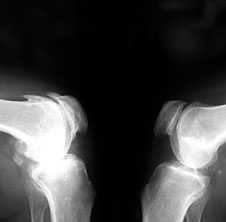

3. Заострение краев суставных поверхностей мыщелков бедренной и большеберцовой кости, чаще в медиальном отделе сустава (связано с большей нагрузкой на этот отдел сустава), особенно при наличии варусной деформации сустава; реже - в латеральной части или одновременно в обеих половинах суставной поверхности (рис. 2).

Рис. 2. Rо-графия коленных суставов в боковой проекции.

Артроз феморопателлярных суставов (больше слева). Артроз коленных суставов (I ст по Kollgren справа, IV ст. по Kollgren слева)

При прогрессировании артроза коленных суставов (соответствует 3-4 стадиям артроза по Kellgren):

• нарастает сужение суставной щели

• развивается субхондральный остеосклероз в наиболее нагруженной части сустава

• появляются множественные крупные остеофиты на боковых, передних и задних краях суставных поверхностей

• редко обнаруживаются субхондральные кисты